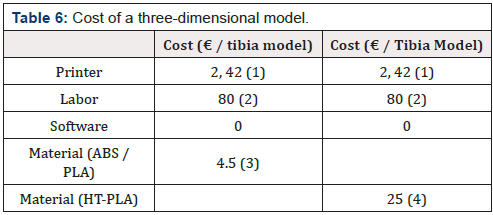

The Innovative Workflow

For the survey we follow the data obtained by analyzing the pilot study [“3D-printing models in the pre-operative planning of the pediatric patient suffering from congenital malformations”][11]. Thanks to 3D printing, the surgeon can better understand the anatomical condition of the patient. The possibility of developing more detailed surgical plans allows the doctor to achieve better results, safety and speed during the operation. The possibilities to refer to the prototype both before and during the intervention should allow a minor use of the fluoroscope. About the post-operative stage, controls are still performed because they are necessary to ensure that the patient is responding well to the operation. The new workflow is illustrated in (Figure 20).

It is observed that, using the prototype during surgical planning, the duration of the intervention is reduced. Decreasing the intervention times allows a lower use of anesthetic dose for the patient lower risk of infection.

The use of 3D models during the pre-operative phase let surgeon proceed with more confidence during surgery due to increased knowledge of the anatomy of that specific case. One of the main advantages of this new method is the radiation time reduction [12]. With the new procedure the first RX scan is no more necessary, and the use of fluoroscopy should be reduced. In addition, the patient could learn the procedure to which he will be subjected interactively through a simulation on the prototype. All this has a positive impact on the hospital as it guarantees an improvement in the service for both patients and hospital staff. There is also a decrease in direct costs. The advantages obtained are summarized in (Table 7).

(Table 8) shows that problems of the traditional method are now solved with the introduction of three-dimensional anatomical model:

Innovative Procedure Profits

Using a three-dimensional reproduction with the new workflow allows to save money in a cost analysis. In the diagnosis phase the number of orthopedic visits fell from 3 to 2 for each patient decrease by 33.4% or saving 18 €/patient. Moreover, the 3D model allows to bypass the first radiological step so the number of radiological visits per patient is halved avoiding the expense of 21 €/ patient. The traditional surgical intervention was about 60 minutes average. Using the prototype, the time frame should be reduced by 15 minutes or 25% less This reduction in use of the operating room costs 206.75 €/ patient less. Finally, studying the case on the 3D prototype decrease the recurrence rate of 15% compared to the traditional case (only CT used). Moreover, with the innovative methodology, one less case of relapse in a year occurs (2 cases compared to 3 in the traditional procedure). In the worst-case scenario, if all 2 recidivist patients need re-intervention, the total saving is about 5094.32€ (new TC: 86.5 €; inspection visit: 18 €; the surgery: 3380 €; post-operative phase: 1627.32 €). (Table 9) summarizes the improvement rates of the new workflow in terms of money saving per year. Looking at the (Figure 21), the saving in the diagnosis phase is 1295,4 €/year, in the surgery phase it is 10258.5 €/year while in the post-operative phase a is 1952.8 €/year for a total saving of € 13,526.7 €/year. It results in a total reduction in spending of 7/8 % per year.

It is also necessary to consider the expense due to the cost of creating a sterilizable prototype, i.e 107.42 €/model since the only suitable from the list before mentioned is HT-PLA. Considering that the number of patient’s 3D models in one year is average 27 (25 new cases and 2 repeat offenders), the total cost is approximately 2900 €/year. Finally, the cost of the innovative method is therefore around 10607 €/year, which allows an annual saving of 6.1 %. The result obtained is based on the worst hypothesis for recurrence cases where re-surgery is considered necessary. It was considered in also the case of zero recidivism for both procedures. Taking account that the production cost of 25 prototypes is 2686 €, the total cost of the proposed procedure is 102943 €/year. The advantages brought by the use of the prototype make the innovative procedure more tempting because of the lower costs also in this case.